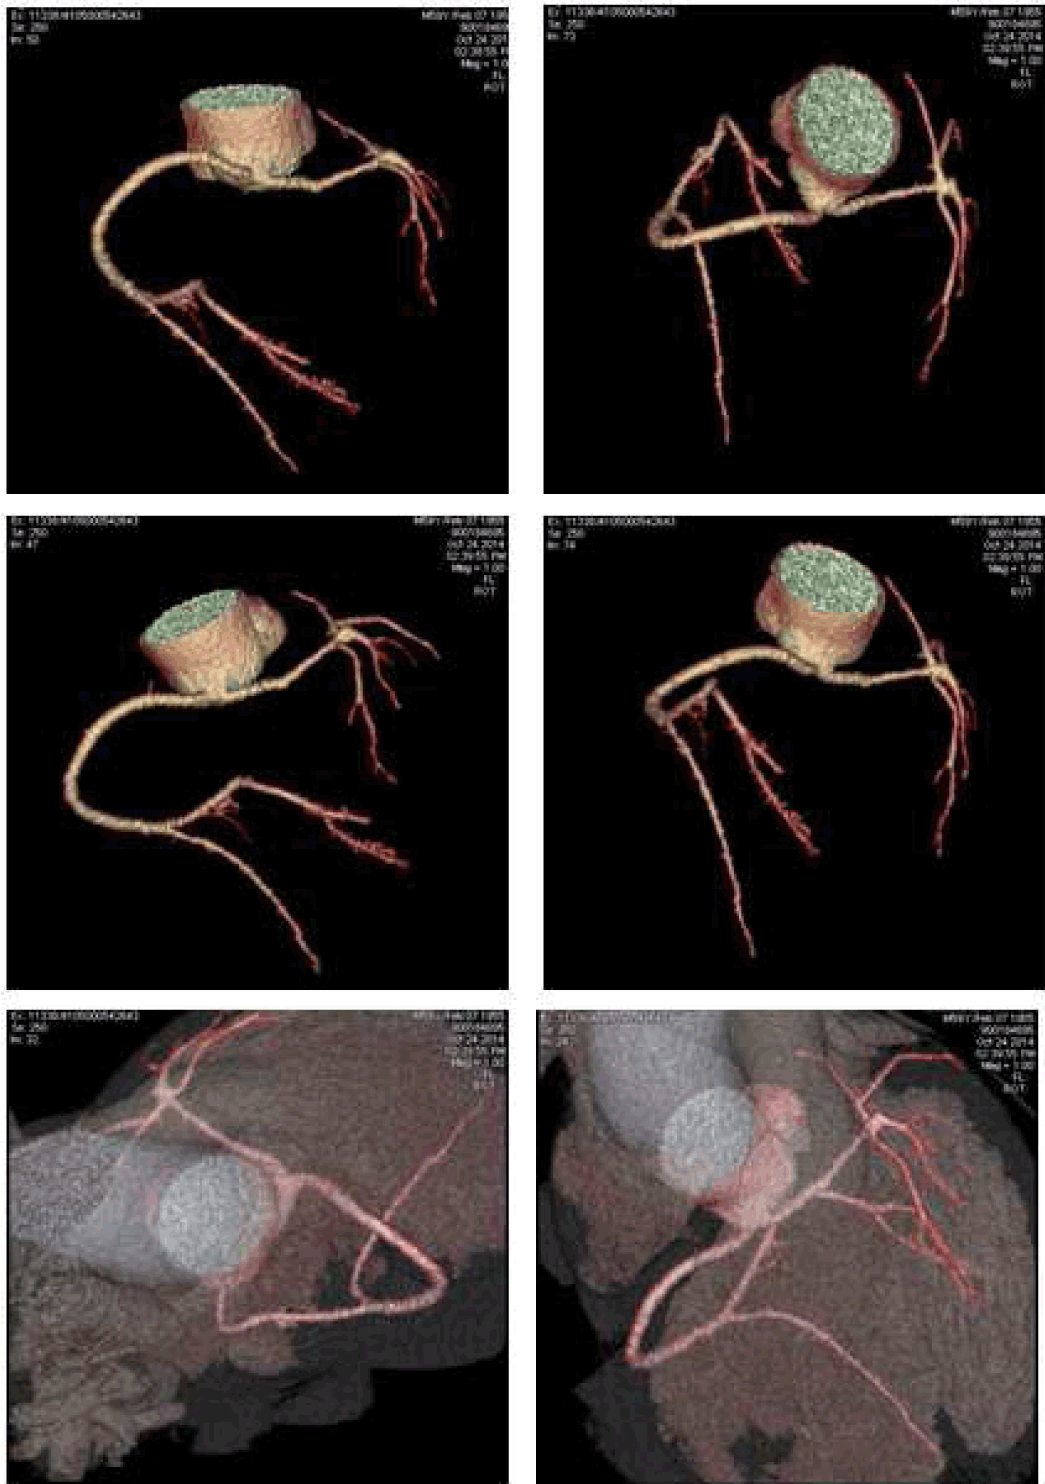

A 45-year-old male was admitted in our department with symptoms characterized by intermittent substernal chest discomfort non-provoked by exertion or emotional stress enlarging for over four months. The patient was a smoker of 7–8 packs of cigarettes per week for 10 years. Clinical history was negative for hypertension, diabetes mellitus, hyperlipidemia or family history of premature vascular disease and no risk factors for pulmonary embolism or respiratory distress. Physical examination showed normal blood pressure (BP: 128/88 mmHg), heart rate of 73 beats/min, no signs of vascular disease and normal cardiac examination. Initial laboratory tests showed no particular anomalies with normal blood levels of glucose and cholesterol (LDL: 103 mg/dl; HDL: 35 mg/dl; TG: 198 mg/dl). Resting electrocardiogram (ECG) showed normal sinus rhythm at 82 beats/min without anomalies in stress examination. Several echocardiographic examinations revealed a moderate enlargement of the left atrium; an apical form of left ventricular hypertrophy; a preserved left ventricular (LV) systolic function (LV ejection fraction, 57%); and moderate mitral valve regurgitation, with no abnormality of the mitral valve apparatus or of LV wall motion. Three months ago the patient had undergone coronary angiography evaluation which demonstrated an anomalous vascular anatomy with absence of coronary ostium in left cusp of the aortic valve and a single coronary artery (SCA) with origin by the right coronary cusp with one and only common trunk (CT) which gives rise to right coronary artery (RCA), left anterior descending (LAD) and diagonal artery, circumflex branch (CB) and the proximal left marginal artery (LMA). The RCA gives off the posterior descending artery (PDA) and the postero-lateral branch (PL). Significant flow-limiting stenosis was not detected with regular caliper representation of the three main coronary branches up to their distal segments. Contrast ventriculography confirmed the apical LVH and showed no wall motion abnormality. In our department, the patient underwent CT scanning, which confirmed the anomalous origin and course of coronary vessels showing also an inter-arterial course of the CT between the pulmonary artery and the aorta (Figure 1) (Figure 2). A 2-cm segment of the proximal-middle tract of the common trunk was embedded within the inter-ventricular septum, following an intramural course with a relative reduction of tunneled vessel (Figure 3). No significant atheromatous alterations have been highlighted, if we except for some parietal irregularities at LAD. Dipyridamole Tl-201 SPECT confirmed a perfusion abnormalities with reversible perfusion defects in the mid anteroseptal wall without an apical abnormality. The patient was admitted to cardiology center for further evaluation, treatment and periodical follow-up. |

Coronary angiography evaluation has demonstrated an anomalous vascular anatomy with absence of coronary ostium in left cusp of the aortic valve. Computed tomography (CT) scanning has confirmed the anomalous origin and course of coronary vessels showing also an inter-arterial course of the CT between the pulmonary artery and the aorta. A 2-cm segment of the proximal-middle tract of the CT was embedded within the inter-ventricular septum, following an intramural course with a relative reduction of tunneled vessel. Thin bridges can be not demonstrable angiography, so anatomic and panoramic CT-evaluation give more information especially if associated with functional evaluation. Knowledge of physiology, normal and variant anatomy, is most important in managing congenital and acquired disease, and variation in coronary arterial patterning is frequent. |